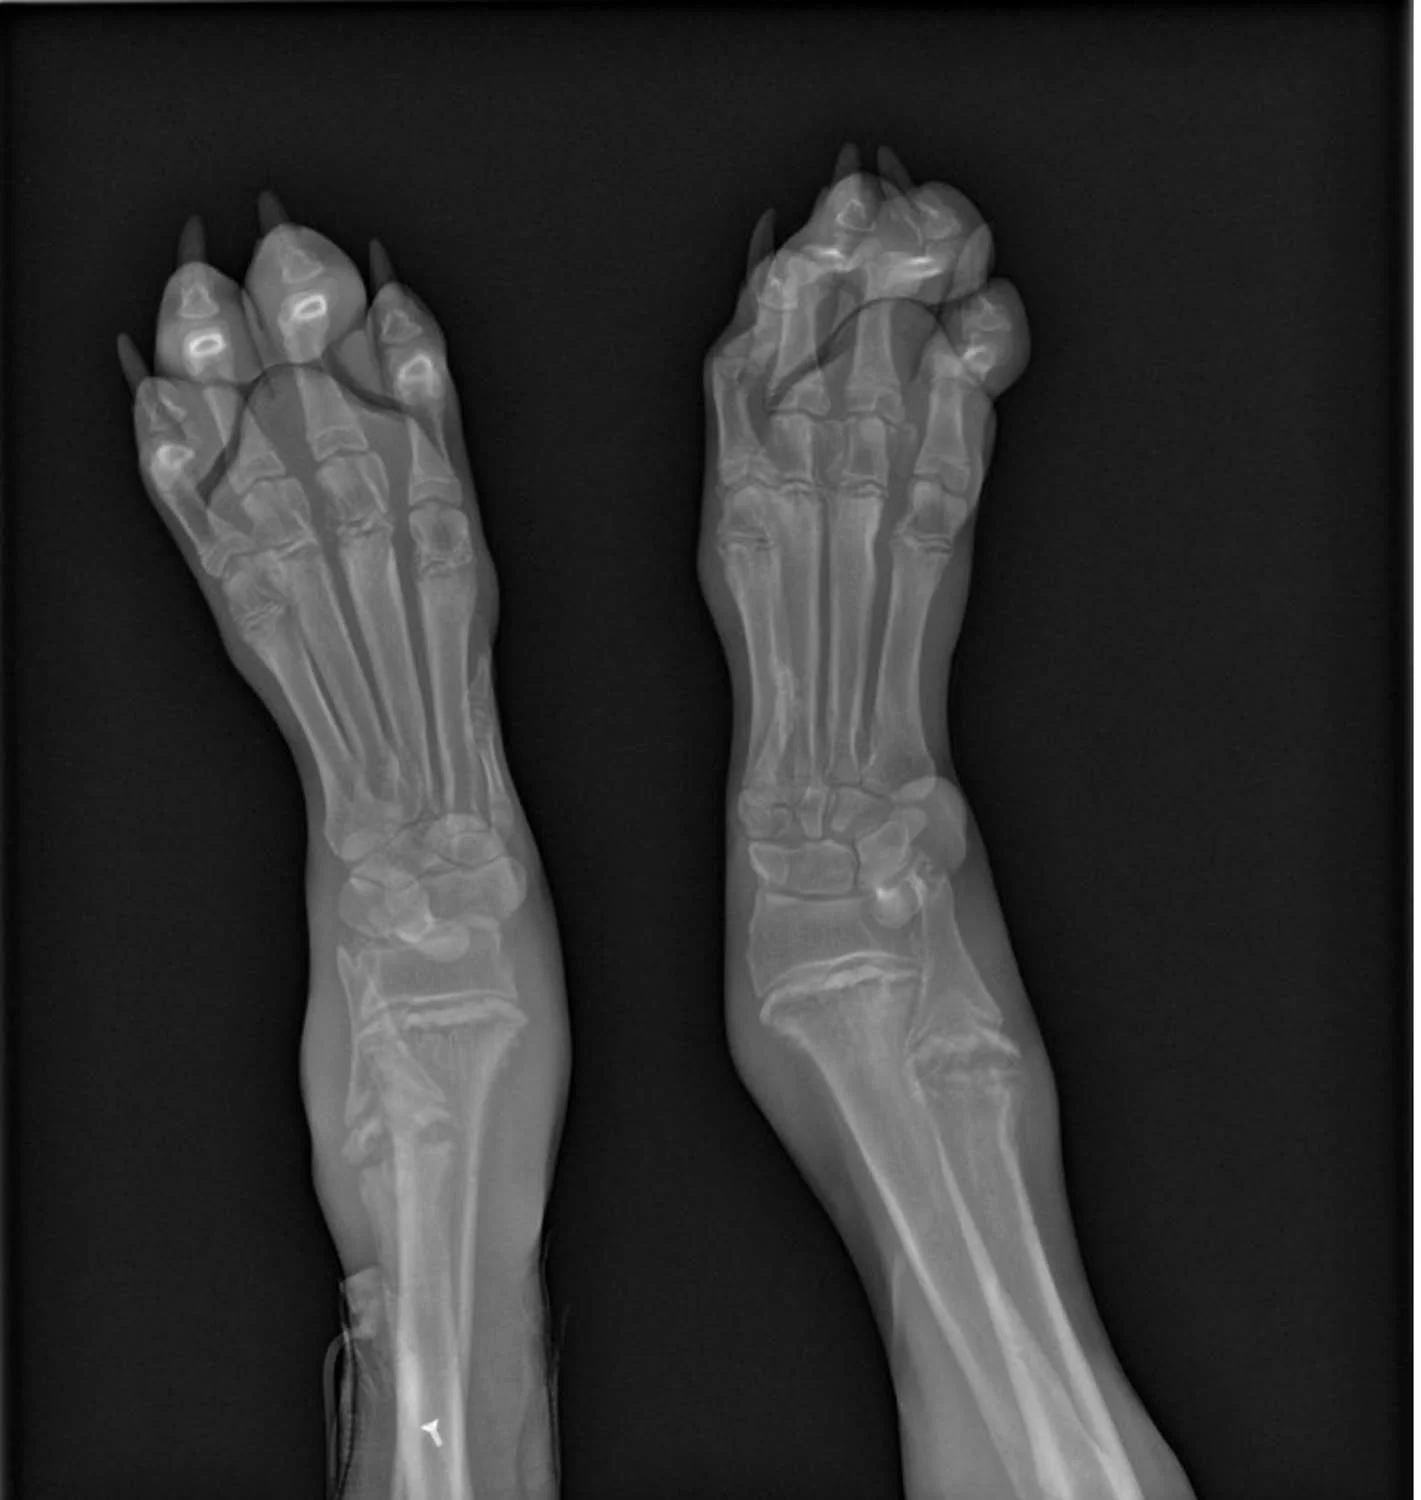

Veterinarians diagnose HOD on the basis of medical history, clinical signs, and by ruling out infectious causes. The most important diagnostic tool is taking radiographs, a type of X-ray. Radiographs can show the typical bone lesions that form in connection with HOD.

hypertrophic osteodystrophy

Radiographs of Bodhi’s Front Leg Bones: July 2012

Below are “before” and “after” pictures of his front legs which were hit hardest by the disease. On the left, you can see how knobby the joints were and that his wrists had no strength and that his paws laid almost flat on the ground. You can see on the right that his legs are far less lumpy and that he’s largely resting on his toes as he should.